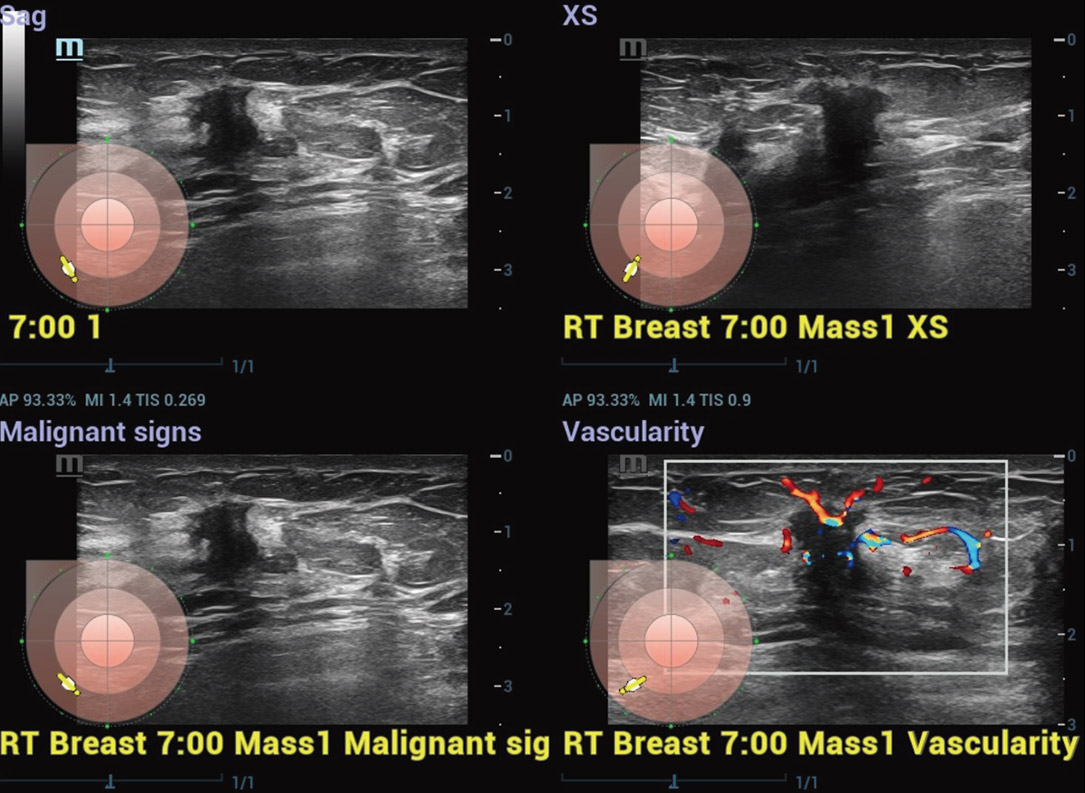

Smart Breast ã Tumor maligno

Smart Breast

O Smart Breast ûˋ uma ferramenta de anûÀlise e gera??o de relatû°rios de ultrassom mamûÀrio para tornar a rotina clûÙnica do ultrassom de mama mais precisa e produtiva. O gerenciamento sistemûÀtico de vûÀrias les?es e a avalia??o em quatro planos garantem ainda mais informa??es diagnû°sticas. Enquanto isso, o fluxo de trabalho automatizado simplificado aumenta a eficiûˆncia na varredura mamûÀria.

cUMA ã Massa mamûÀria

Massa mamûÀria

CEUS ã Massa mamûÀria